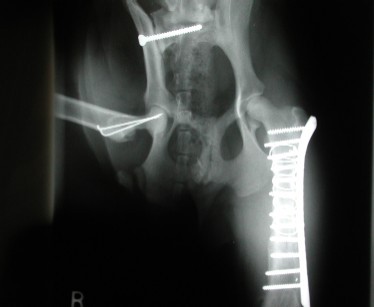

![]() |

Rontgen dari Pelvis yang patah |

| Foto Rontgen dari pelvis yang telah dilakukan operasi |